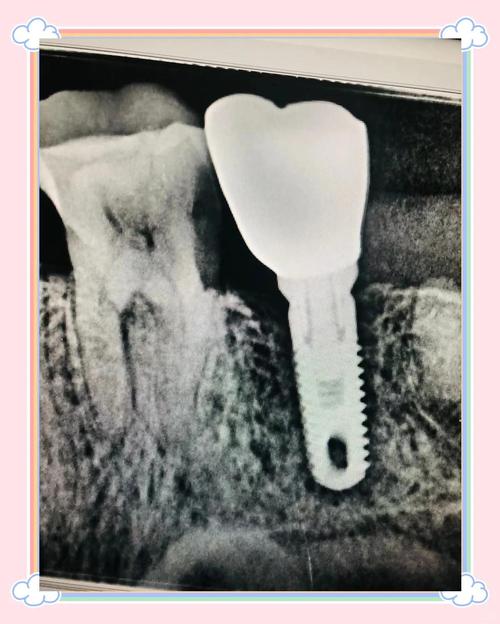

- 种植体:由生物相容性极高的纯钛或钛合金制成,通过外科手术植入牙槽骨内,其表面通常具有特殊的螺纹或粗糙结构,能与骨组织形成稳定的“骨结合”(osseointegration),成为支撑上方结构的“地基”,这部分完全位于牙龈下方和骨内,正常情况下无法被肉眼直接观察到。

- 定期复查:医生通过X光片检查骨结合情况,观察牙槽骨是否有吸收,同时检查牙冠磨损、基台稳定性等,确保“隐形”的种植体始终处于健康状态。

A:种植体的牢固性可通过临床检查和影像学评估确认,医生会通过叩诊(轻敲牙冠)检查有无松动,或用器械测试种植体动度;同时通过X光片观察种植体与骨组织的结合情况,若骨结合良好,种植体周围骨密度均匀、无透射影,则表明其牢固可靠,患者日常若感觉牙冠咀嚼有力、无疼痛或松动,通常也预示种植体状态稳定。